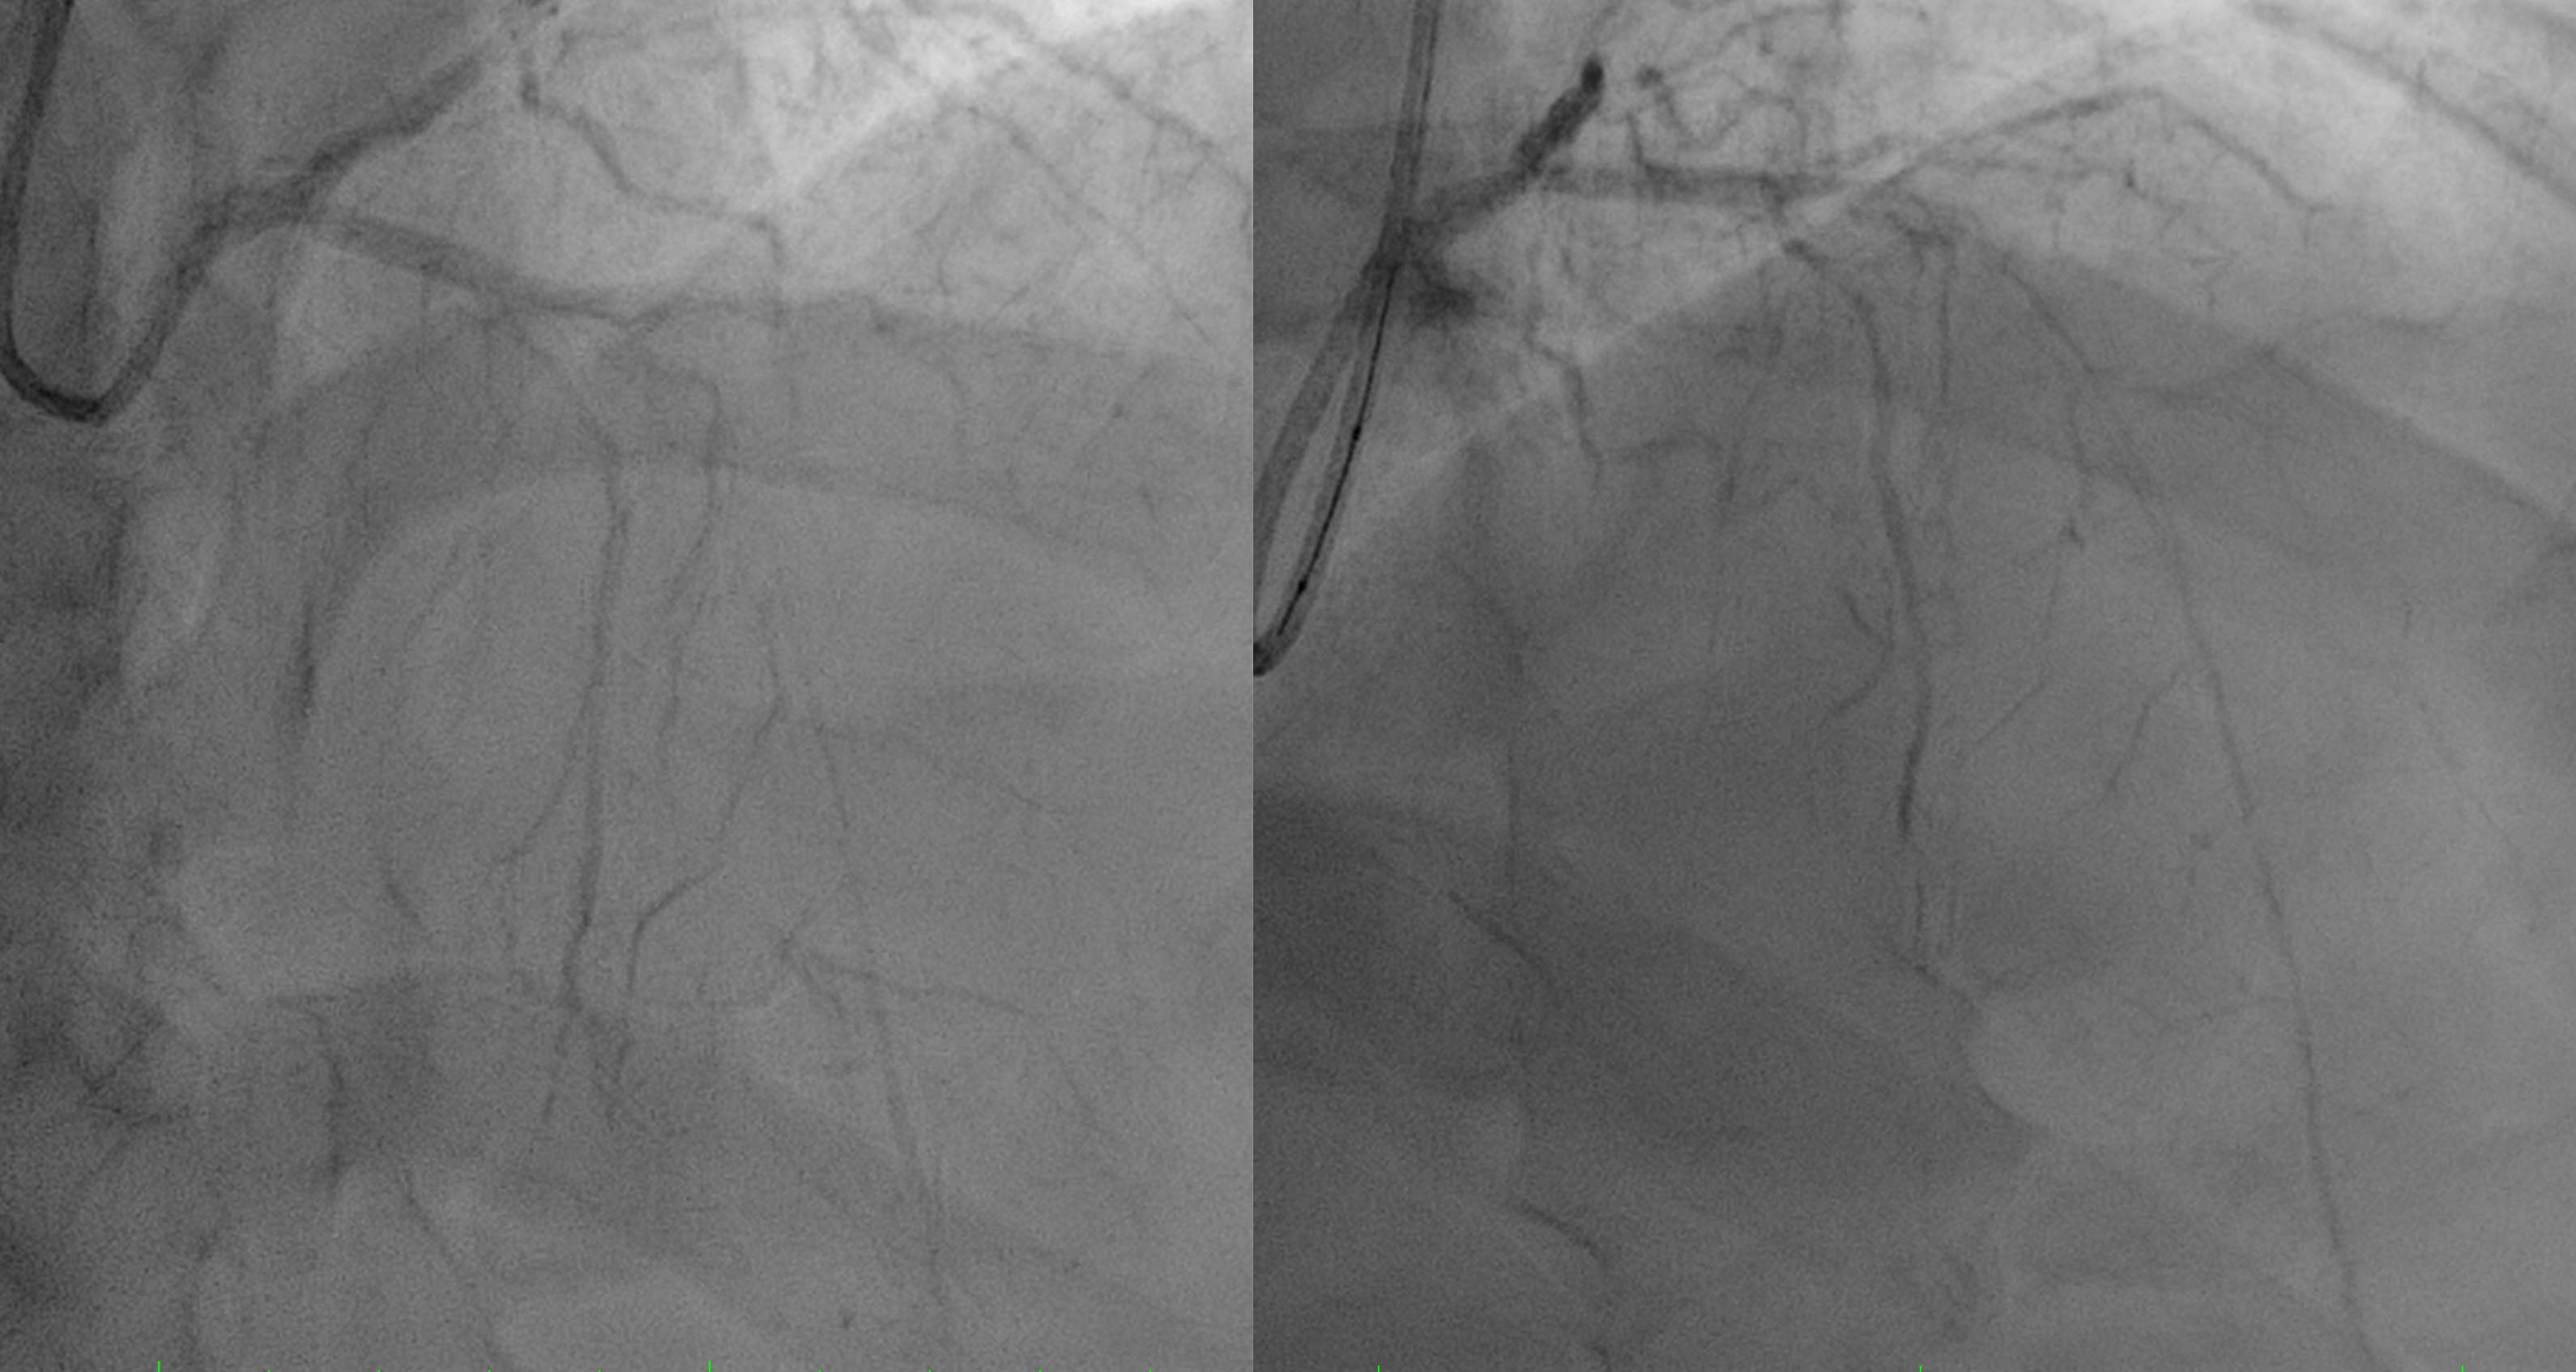

First patient was done thrombolytic therapy and failed, was done angiography with thrombus in LAD and LCx. We did thrombus aspiration and get TIMI 2 flow.Second patient was done primary PCI and having only POBA due to ambiguous distal LAD

first patient using Guidewire Runthrough to LAD and done Thrombus Aspiration and move to LCx to do Thrombus Aspiration. Patient was given eptifibatide bolus. But thrombus still high burden but already have better flow so we stopped case and heparinized. Second patient was having CTO LAD, wire with Pilot 50 but then escalated to Pilot 150. We could puncture the proximal cap, done POBA proximal with small balloon 1.5x15 mm and then up to 2.5x15 mm but the distal wire we suspect not in true lumenso we stopped the case after having better view distal LAD.